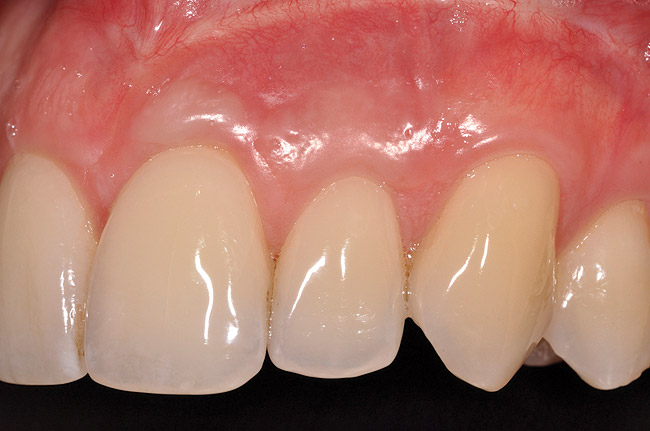

Various procedures to correct deficient gingival contours have been well documented in the dental literature.1,2 Increasing zones of attached gingiva using palatal donor tissue and the free gingival grafting procedure was introduced by Björn almost a half century ago.3 Using palatal donor tissue in the form of a free soft-tissue autograft for root-coverage procedures was reported by Miller.4 Additional procedures were reported using lateral5 or coronal repositioning6-8 of the adjacent attached gingiva via a pedicle flap or the coronal repositioning of previously grafted tissue.9,10 Miller also reported on gingival grafts placed over root surfaces to correct areas of deep-wide gingival recession.11 Further surgical advancements led to the use of subepithelial connective tissue from the palate to obtain root coverage.12-14 Figure 1 shows the pretreatment view of a mandibular central incisor, and Figure 2 depicts the post-treatment view of the site treated with a subepithelial connective tissue graft harvested from the patient’s palatal tissues.

Once the flap was coronally repositioned and secured, a securing periosteal tac procedure was performed to prevent any micro movement superior to the mucogingival junction in the initial healing phase. A 4.0 chromic gut suture (Surgical Specialties Corp.) was used to engage the periosteum superior to the mucogingival junction and stabilize the tissues superior to the securing suture (Figure 12 and Figure 13). Multiple periosteal tac sutures may be necessary, depending on the size of the surgical field. Postoperatively, the periosteal tac sutures are routinely removed if not totally absorbed at 7 days; the flap sutures are removed at 2 to 3 weeks, and dermal-securing sutures are removed 1 month after surgery. The 1-year post-treatment clinical view shown in Figure 14 depicts the excellent soft-tissue result, band of attached–keratinized tissue present, and excellent color match to the host gingival tissues.